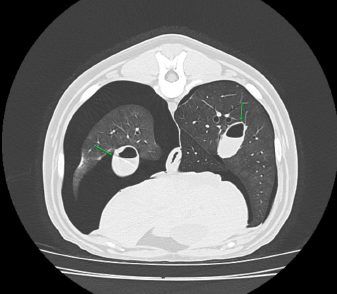

Case details for each of the five dogs included in the study are listed in Table 1. The etiology of the pneumothorax were congenital pulmonary bullae in two dogs, traumatic in one (road traffic accident), lungworm infection in one, and unknown in the remaining dog. Dog number 1 presented a large pulmonary bulla in the right cranial pulmonary lobe (Fig. 1). Dog number 2 presented four bullae: two in the medial aspect of the left cranial lung lobe (17 mm each), one in the caudal aspect of the left caudal lung lobe (26 mm), and another in the caudal border of the left caudal lung lobe (36 mm) (Fig. 2). Dog number 3 presented a large bulla measuring 33 mm in the medial aspect of the right middle lung lobe and around 10 blebs measuring from 3 to 6 mm in the ventral border of both right and left cranial lung lobes. Dog number 4 developed multiple small bullae and a larger one measuring over 10 cm, 24 hours after treatment of lungworm with spot on Imidacloprid and Moxidectin, which were responsible for a moderate unilateral pneumothorax (Fig. 3). Despite the severity of the pneumothorax, dog number 5 did not show any lesions on the computed tomography (CT) scan that could clearly explain its origin. Only one chest tube was placed in dogs 1, 2, 3, and 4. Two were placed in dog 5.

Fig. 3. Right-lateral thoracic radiograph of a 9-month-old female dog (dog number 4) suffering from a pneumothorax secondary to lungworm infection.